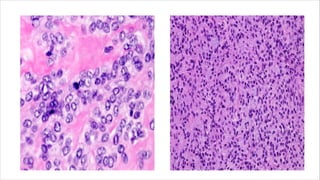

• Composed of small to large epithelioid cells with vesicular nuclei

with central nucleoli.

• Rare or absent mitoses and necrosis.

Epithelioid variant of pleomorphic

liposarcoma

• Rare variant of liposarcomas.

• Peak incidence in seventh decade of life.

• Occurs in extremities.

• Aggressive often exhibiting local recurrence and metastases.